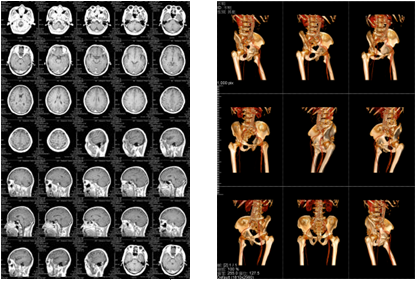

膠片紙輸出樣張示意--科頤辦公分享

膠片紙輸出樣張示意

成本優化兼具環保一舉兩得

該三甲醫院放射科負責日常CT、核磁共振影像的輸出,平均的日打印量在1000張左右。在導入解決方案前,該放射科的影像輸出使用干式膠片打印傳統膠片,輸出設備價格不菲,而且傳統膠片價格更是高昂。另外,傳統膠片不能實現彩色輸出,醫生必須在背光板上進行診斷,膠片本身還含有重金屬等有毒物質,污染環境。為此,柯尼卡美能達向專業供應商采購了DICOM轉換服務器和符合醫院要求的打印膠片紙,可實現三維打印,打印的影像可直接在自然光下觀看,便于醫生診斷;膠片紙的成本是傳統膠片的三分之一而且不含毒物質,既節省成本又綠色環保。